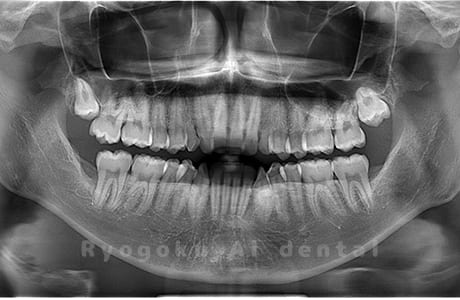

Case03

- 原因

- 上顎、下顎の親知らず

- 治療内容

- 上下4本の親知らずを抜歯したケースです。

<リスク・副作用>

手術後は痛み、腫れ、痺れなどの副作用が生じる場合があります。